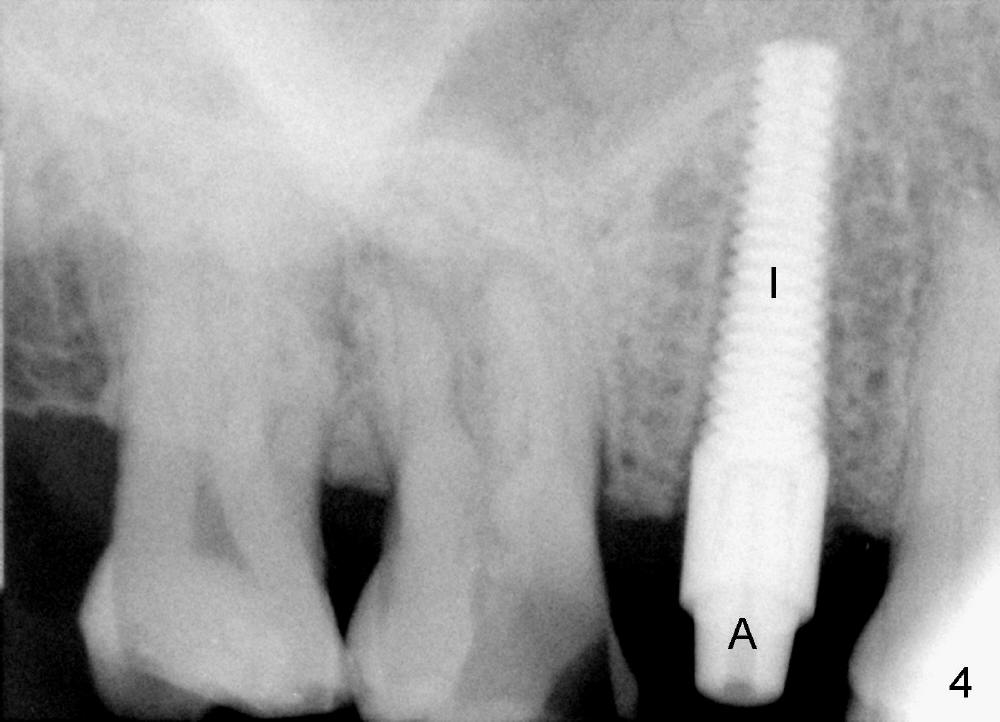

A 72-year-old man is a bruxer with #3 cusp fracture with chronic periapical radiolucency (Fig.1 *) and #4 acute crack. It appears reasonable to take care of emergency (#4 extraction and immediate implant (Fig.3-7: 4.5x20 mm, 45 Ncm)) followed by root canal therapy or extraction for #3. Eight (Fig.8) and 14 (Fig.9-11) days postop, the patient is doing fine and the wound heals normally. But he does not agree any treatment for #3, since it is asymptomatic in spite of a fistula associated with the tooth (Fig.8,9 >). Three months postop, the patient is still asymptomatic and is ready for #4 restoration since the tooth #28 cracks. Follow-up PA shows the persistent distal gap (Fig.12 >, as compared to Fig.4), accompanied with crestal bone resorption (*). Clinically the implant has mild mobility and light tenderness. The patient still refuses #3 treatment. It appears that the implant has failed to osteointegrate. In brief, do not place an immediate implant next to active infection.

Five and a half months postop, the distal gap appears to have reduced (Fig.13 >). Clinically the implant is stable and is ready for restoration. It is advisor able to watch those asymptomatic immediate implants with minimal mobility. It takes time to osteointegrate the immediate implant considering the peri-implant space.